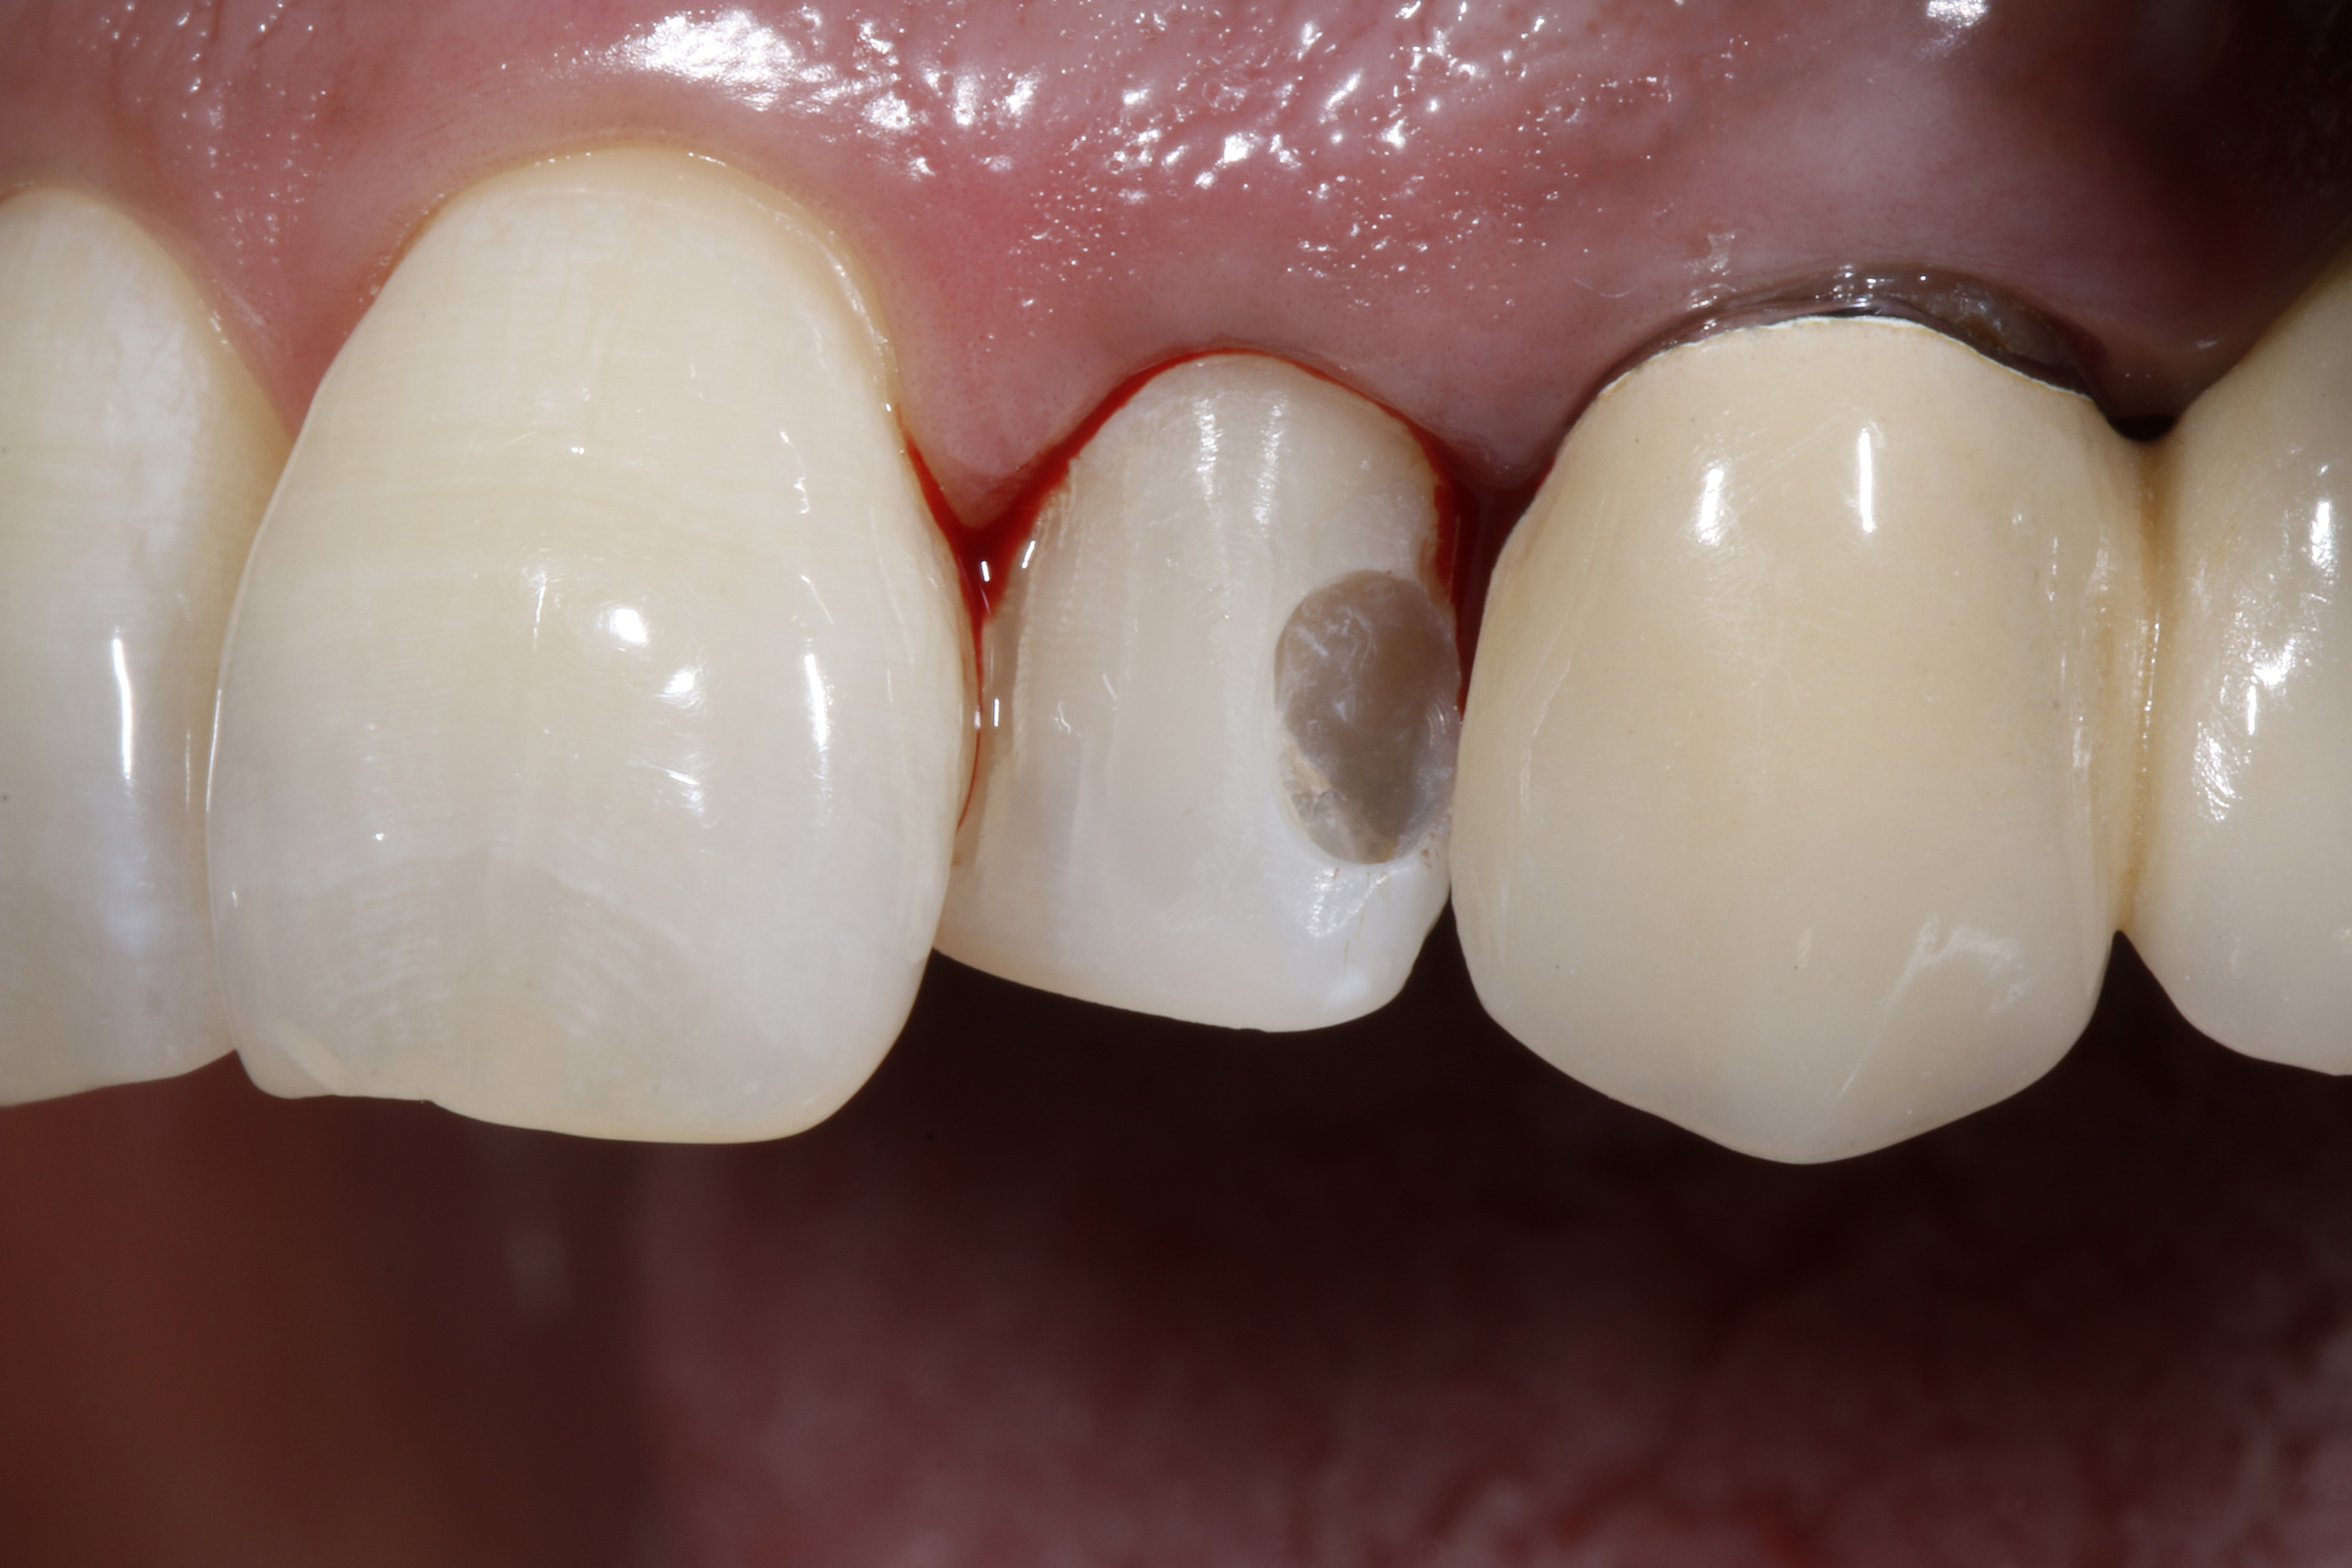

Do naszego gabinetu stomatologicznego zgłosiła się 60-letnia pacjentka z prośbą o lepsze optyczne ustawienie w łuku zębowym lewego bocznego siekacza szczęki, który jest wyraźnie położony podniebiennie w stosunku do lewego siekacza centralnego (ryc. 1 i 2).

Oprócz samego zęba, pacjentce szczególnie przeszkadzał fakt, że ząb wydawał się znacznie ciemniejszy w uśmiechu w porównaniu z lewym siekaczem centralnym i koroną PFM na lewym kle. Ząb bezzwłocznie zareagował nadwrażliwością na test na zimno, nie wykazał przy tym nieprawidłowości w teście opukiwania. Po zapoznaniu się z możliwymi alternatywami leczenia i ich kosztami, pacjentka zdecydowała się na licówkę bezpośrednią z użyciem uniwersalnego kompozytu GrandioSO Unlimited (VOCO GmbH, Cuxhaven).

Ryc. 1, 2. Sytuacja wyjściowa: lewy siekacz boczny jest ustawiony wyraźnie podniebiennie w stosunku do zębów sąsiednich. To przeszkadza pacjentce, który chciałaby uzyskać lepszą integrację wizualną z łukiem zębowym.